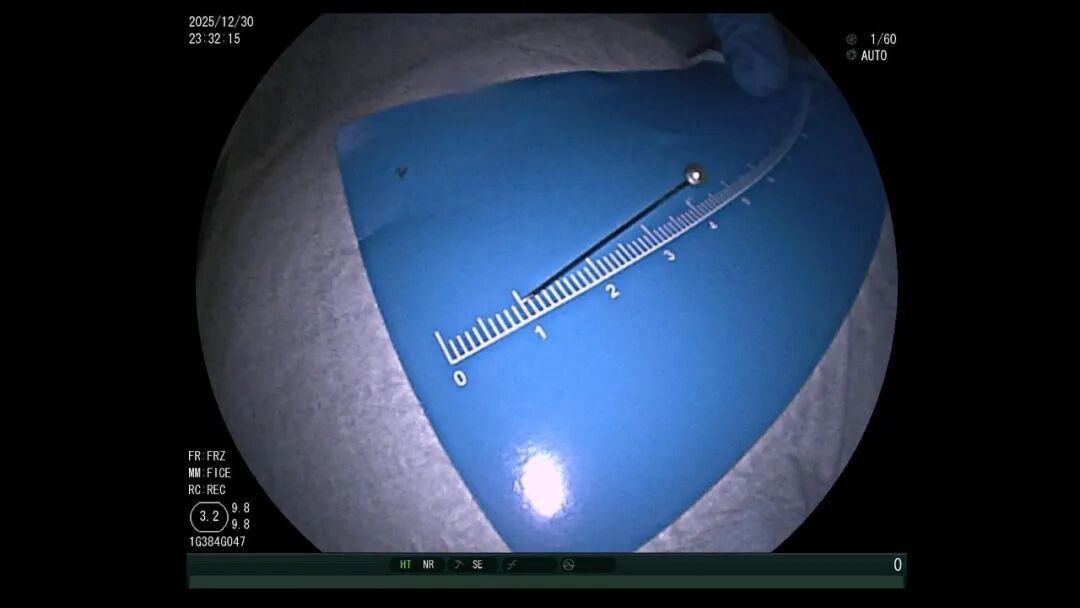

异物找不着:3.5 厘米的大头针混在胃里的食物残渣中,要把它找出来,难度堪比大海捞针。

一开始,医生尝试用异物钳、网兜抓取,但大头针太滑,几次尝试都失败了。紧急调整方案后,医生改用圈套器,在透明帽的辅助下,小心翼翼地将大头针调整为竖直方,避免取出时横向划伤食管。

医生一边指导孩子配合,一边稳稳操控圈套器,将大头针牢牢固定。随着内镜缓缓退出,大头针终于被完整取出,全程未造成任何黏膜损伤。